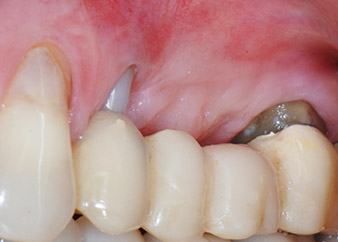

Междинен резултат след два месеца

Фигури 17 и 18 показват клиничния резултат два месеца след операцията. Зъб 24 показва намалена подвижност на Милър клас 1 и меките тъкани не са възпалени. Сондирането е избегнато на този етап, за да се избегне повторно възпаление и нарушение на епителната надстройка. Планиран е контролен преглед за повторно отваряне и поставяне на оздравителни абатмънти, шест месеца след поставяне на имплантите.

Два месеца след операцията, пациентката не чувства болка.

Фиг. 17: Два месеца след операцията, пациентката не чувства болка и зоната не е възпалена.

след операцията

Фиг. 18: Зъб 24 вече показва по-малко подвижност.